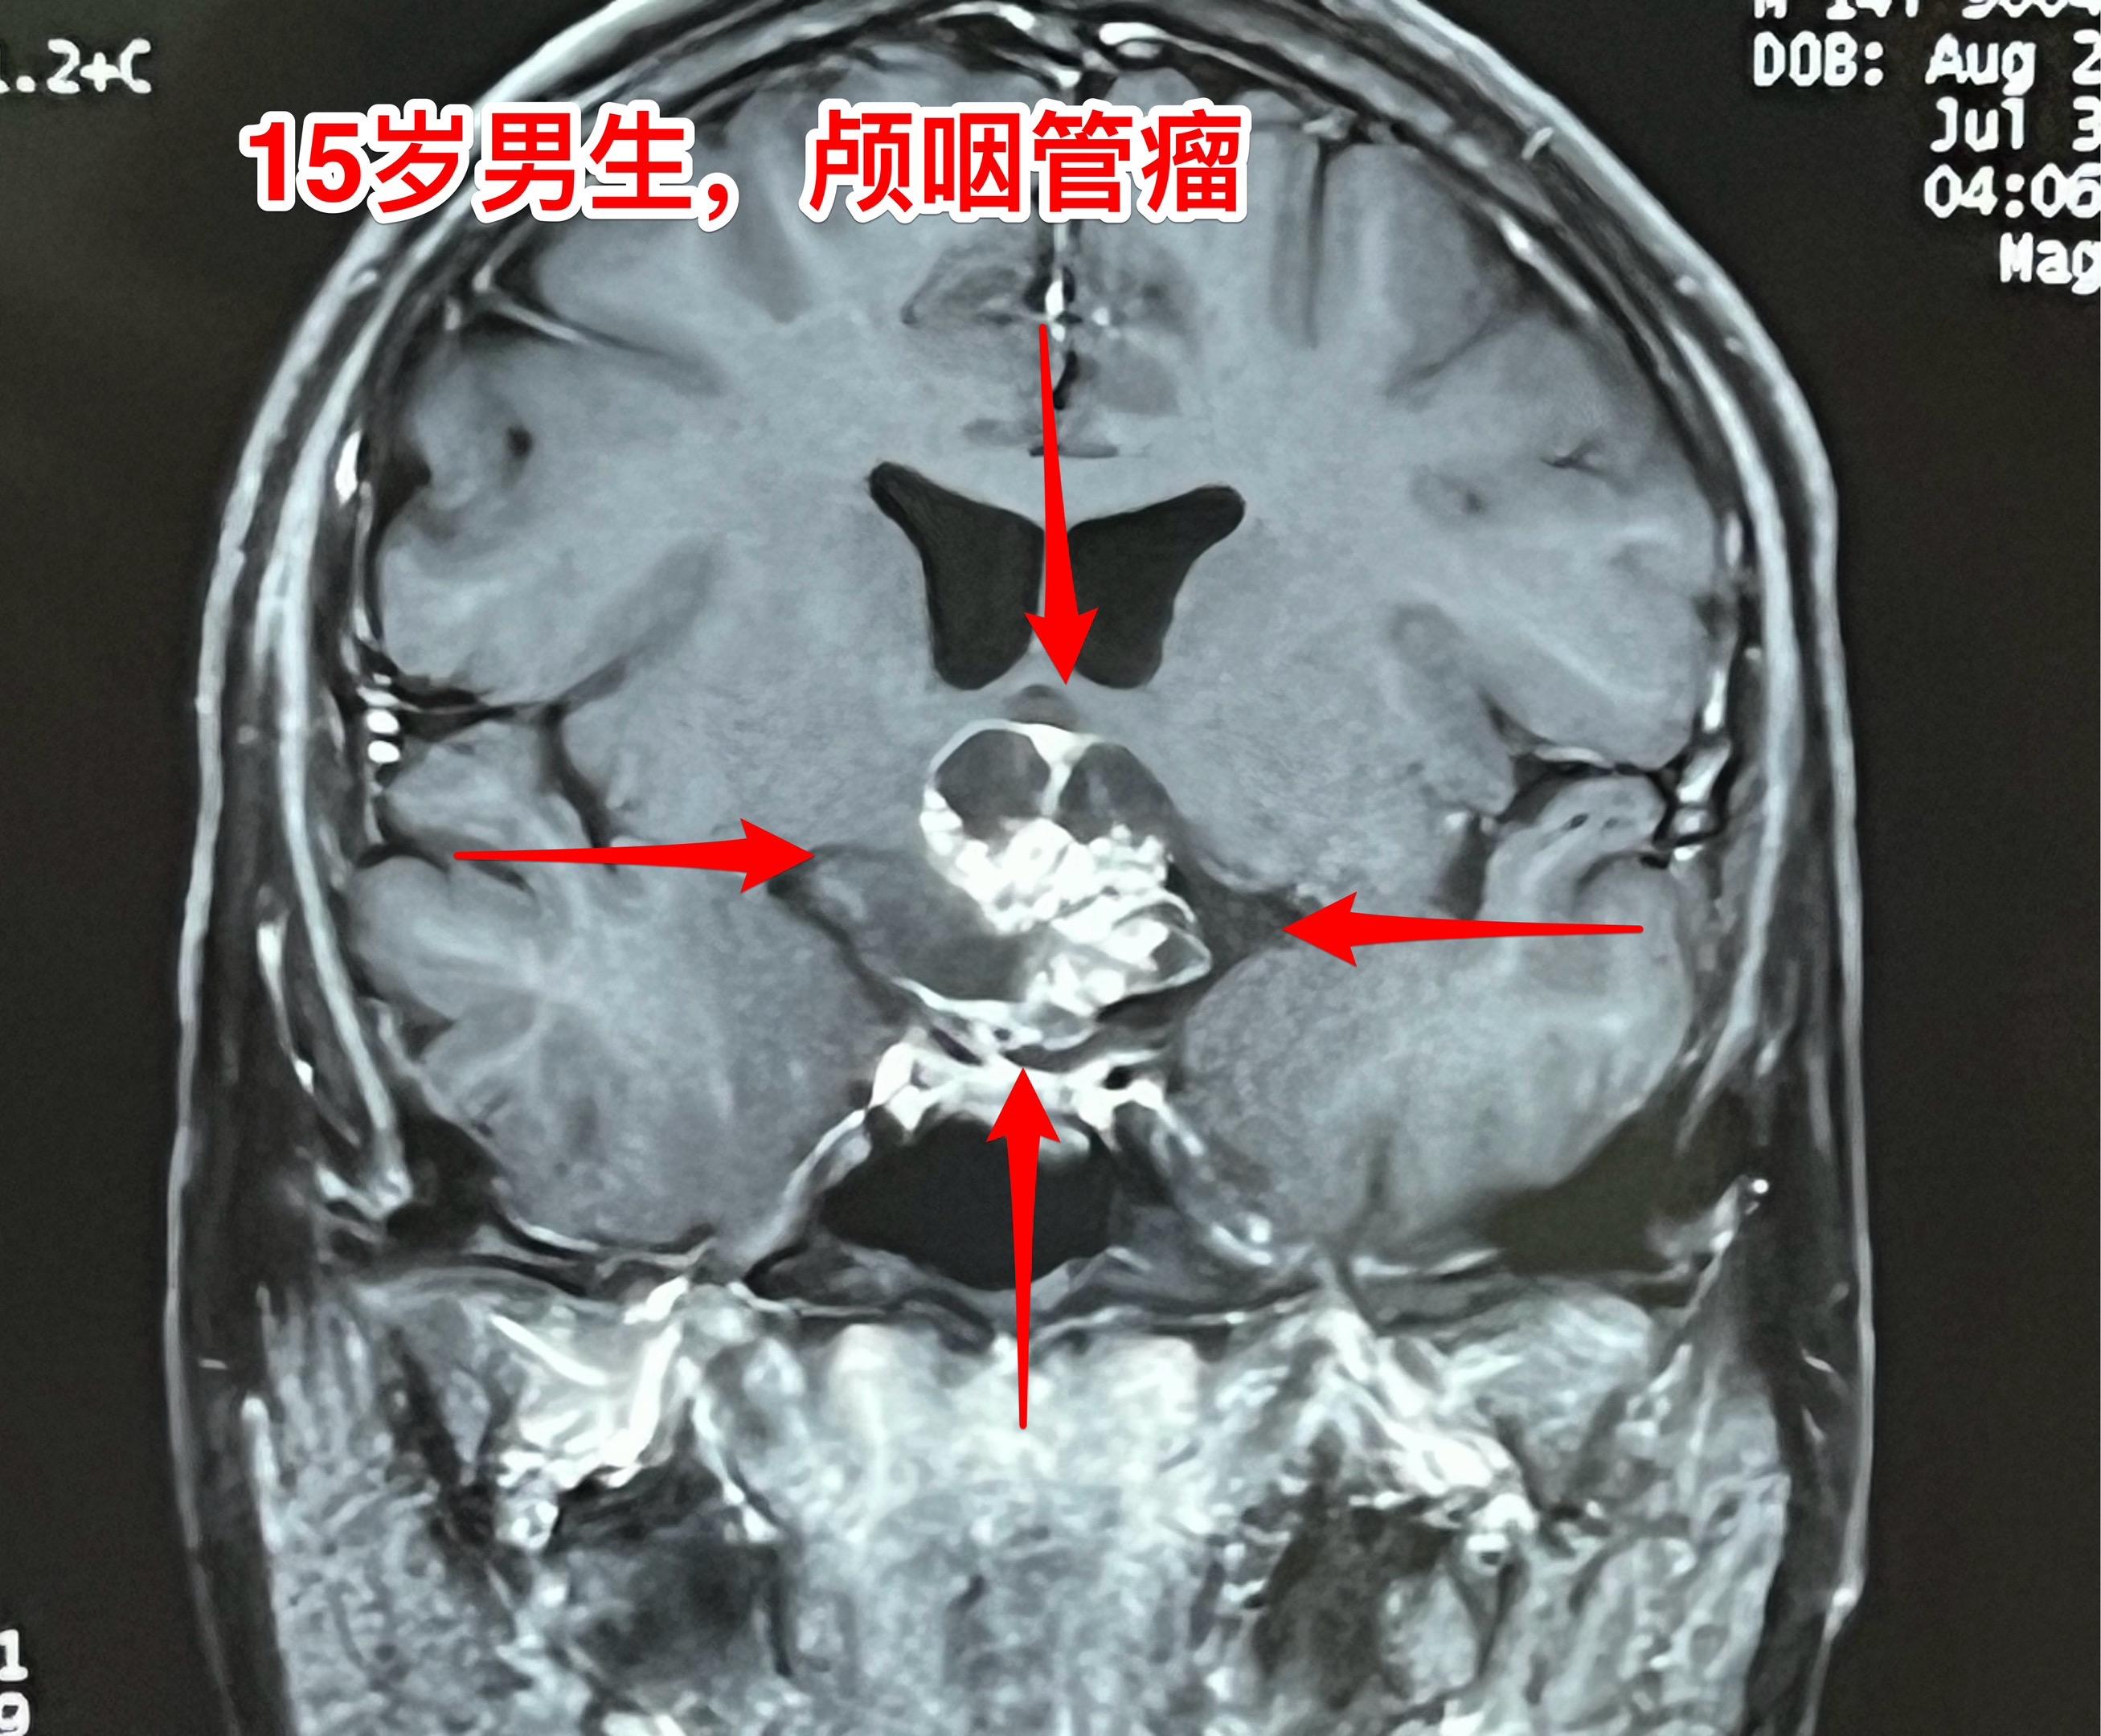

周日加班完成两台颅咽管瘤手术(第167)2025年10月26日(周日)完成了今年的第167例、168例颅咽管瘤手术。 第167例病人,59岁男性,甘肃省武威市人,因视力下降、思维糊涂到医院检查发现颅咽管瘤。 第168例颅咽管瘤患者是15岁的男生,江西省南昌市人,有头痛症状、视力下降症状,但是并未就医。偶然因骑自行车与别人相撞,到医院作头部CT才发现了这个颅咽管瘤。 这两个手术都不简单,肿瘤位置稍有不同,颅咽管瘤均得到完全切除。今天看见两个病人的精神状态均好!